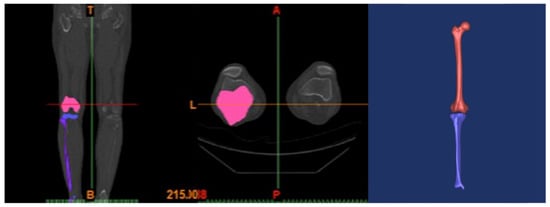

2.1. Intact Model

2.3. Surgical Simulation Model